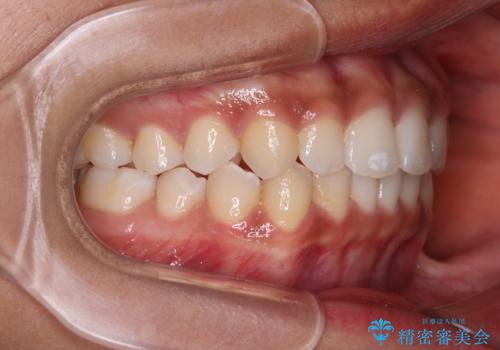

前歯のデコボコを治したい インビザライン・モデレートによる矯正治療

- 上下前歯の叢生を気にして来院された患者様です。

インビザラインでの治療を希望されていて、デコボコの程度が中等度であり、安価なパッケージにて対応可能と判断されたため、インビザライン・モデレートを用いて矯正治療を行うこととしました。

インビザライン・モデレートは、製作できるアライナーの枚数に制限があるため、移動可能な量に限りがあるものの、インビザライン・ライトよりも枚数が多いため、幅広い症例に対応可能です。